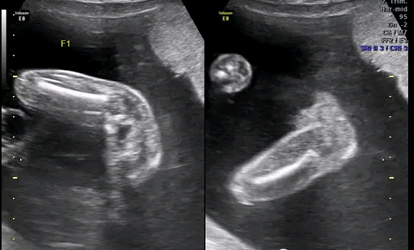

第二,穿刺术前应B超确定胚囊的排列方位并记录,以便术后观察或再次减胎术。

第四,手术中应反复仔细超声检查,确认被减灭的胚胎已死亡,术后l天及1周需再次B超检查,确认多余胚胎的胎心搏动已消失、胚芽模糊,剩余胚胎胎心搏动正常、胚囊完整,对第1次减胎失败而胎儿恢复心脏搏动者,最好及时进行第2次减胎。